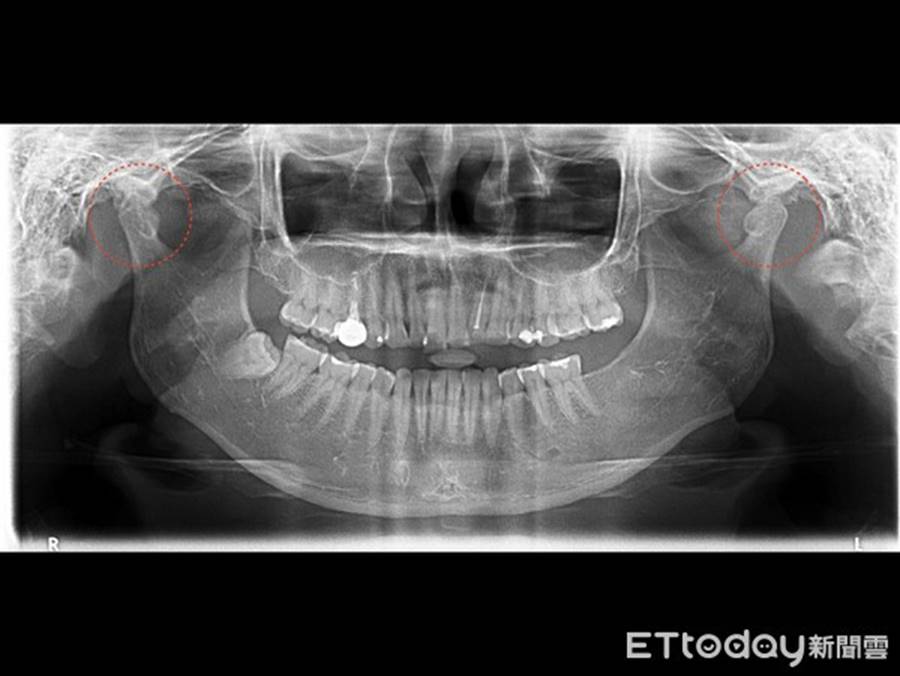

Bác sĩ Hiên chẩn đoán trường hợp của cô Hồng là viêm khớp thái dương hàm, khi há ngậm miệng phát ra tiếng kêu ở khớp, mỗi khi bệnh nhân há hay ngậm miệng đều khó khăn, cơ nhai bởi vì dùng lực quá độ mà dẫn đến căng cứng, ngay cả khuôn mặt của bệnh nhân cũng bị biến dạng.